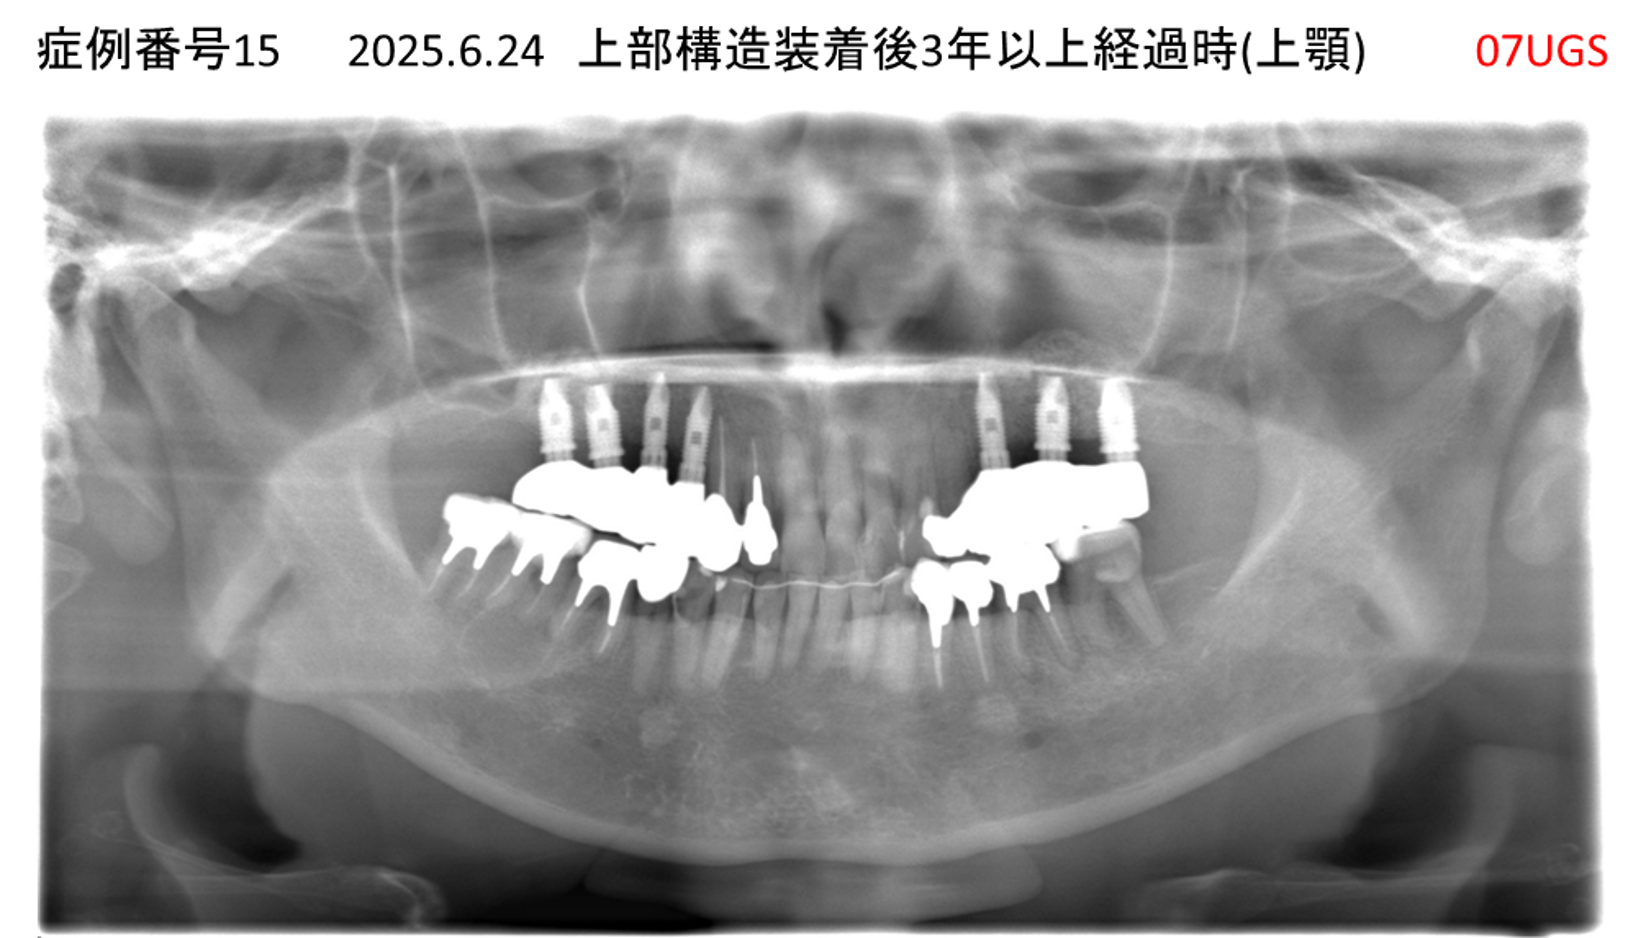

上の前歯が揺れてきてかめない患者様のインプラント症例

| 治療名称 |

インプラント |

| 治療費用 |

335万円+税 |

| 治療期間 |

4か月 |

| 患者さんの症状(主訴) |

上の前歯が揺れてきて噛めない |

| 治療内容 |

サイナスリフト 抜歯即時インプラント |

| 治療結果 |

ちゃんと噛めるようになった。不安がなくなった。見た目がとても良くなったのすごくうれしい。 |

| 治療の注意点(リスク/副作用) |

インプラントが壊れたら再治療が必要 |